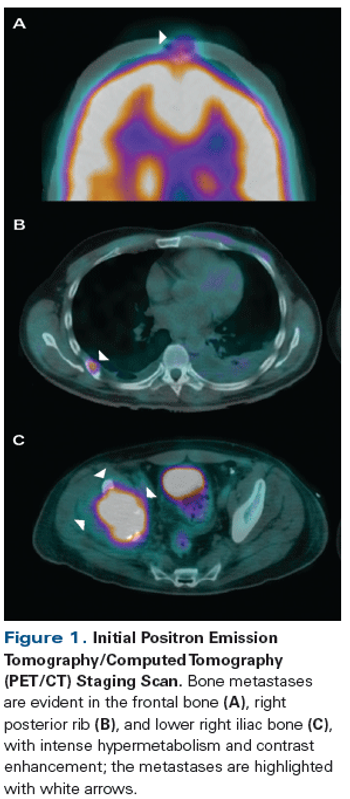

ByMaría T. Bourlon, MD, MSc, FASCO,Monica Meneses-Medina, MD,Sara Vázquez-Manjarrez, MD,Francisco M. Bustamante-Romero, MD,Adriana C. Gallegos-Garza, MD,Elaine T. Lam, MD A 42-year-old man presented with increasing right hip pain that limited his ability to walk. Magnetic resonance imaging (MRI) revealed a right lytic acetabular lesion. Further work-up included a computed tomography (CT) scan, which revealed an 8-cm left kidney tumor.